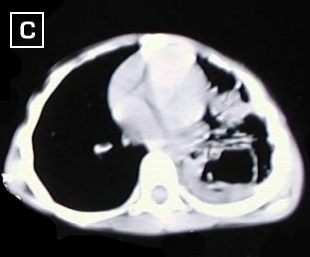

Cortes tomograficos A - B - C - D : Desde carina hacia base del tórax, dezplazamiento de la carina a la derecha, severo engrosamiento pleural izquierdo, con tabicamiento, disminucion del volumen del hemitorax izquierdo, además reporta areas de atelectasia pulmonar en lóbulo inferior izquierdo.